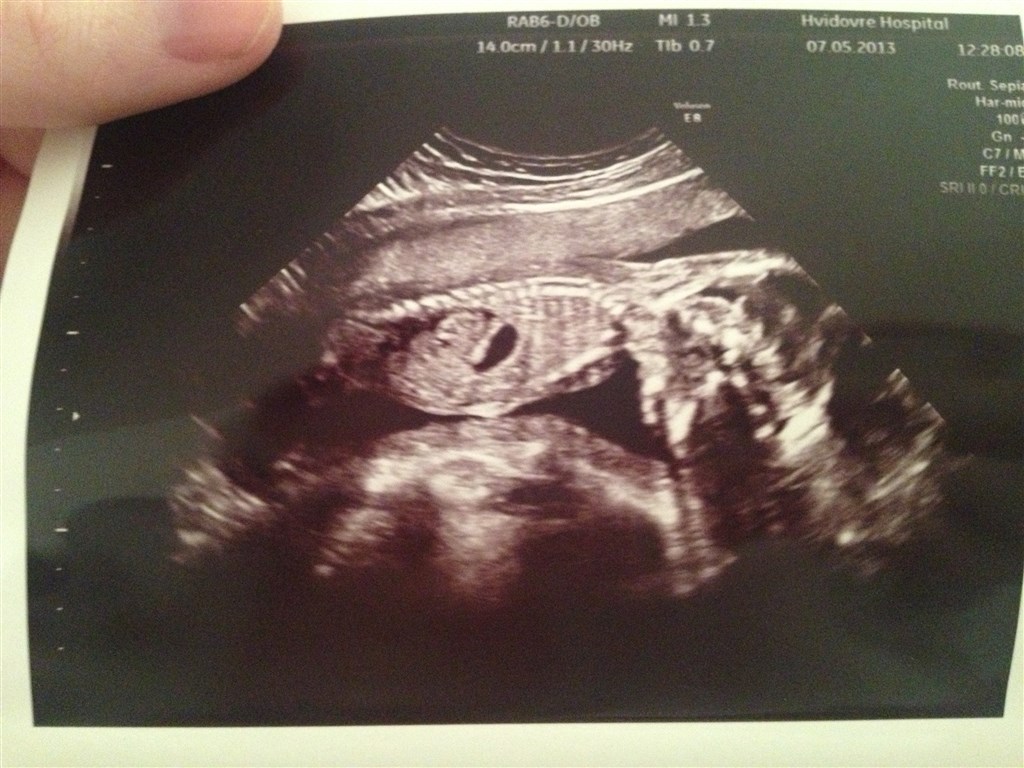

Som bare gik helt fantatisk dog var bassen på ingen måder samarbejdesvillig og han lå på maven og havde en ide om at vende sig ligemeget hvad hun gjorde. Og når hun så begyndte at scanne begyndte han og bevæge sig. Men hun fik set det hun skulle. Og vi fik bekræftet på scanning med egne øjne at han er en dreng har jo kun papir på det fra moderkage prøven

og det som han havde på halsen er helt forsvundet, så nu skal jeg ikke til flere skanninger

og lige et billede af bassen selvom han ligger på maven.